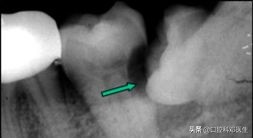

危害二:蛀牙

向前倾斜的阻生智齿,会与邻牙形成一个三角形的间隙,这个间隙易积存食物,而平时刷牙又不能及时完全清除,久而久之就会导致智齿本身以及邻牙(下第二磨牙)龋坏。这种龋坏位置比较隐蔽,不易早期发现,一旦发生疼痛(急性牙髓炎),牙冠常已被严重破坏。即使进行根管治疗,也难长久保存。